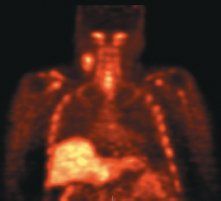

In head and neck cancer, FLT-PET could be used to identify how much marrow has been suppressed after radiotherapy (see Figure). In a study done by Dr. Graham's group at the University of Iowa, the FLT uptake and change early after treatment in squamous head and neck tumors was adequately characterized with SUV obtained at 45 to 60 minutes and correlated well with other post-treatment markers (J Nucl Med 50:1028-1035, 2009).

Top, baseline FLT-PET scan showing radiotracer uptake in right neck nodes and normal distribution of FLT in the bone marrow and liver. Follow-up FLT-PET scan (Bottom and Top Of Article) after 10 Gy of radiotherapy and one cycle of chemotherapy. The uptake in the right neck nodes is decreased. There is also complete disappearance of FLT uptake in the irradiated bone marrow in the cervical spine consistent with marked reduction of cellular proliferation. Images courtesy of Yusuf Menda, MD, and the Universtiy of Iowa department of radiology.